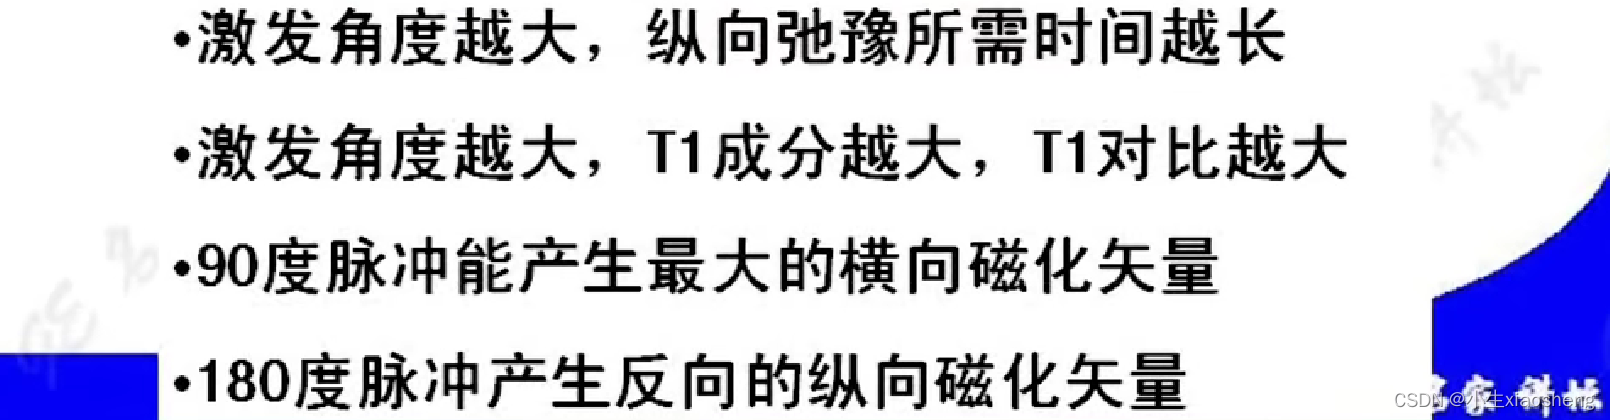

T1(纵向弛豫时间):当射频脉冲信号解除后,激发状态的氢原子核会慢慢释放能量,同时相位和能级会恢复到开始状态、磁化矢量也会恢复到平衡状态。这个过程被称为纵向弛豫

选择合适短的TR获得最好的T1对比:一般TR选择两种组织生物T1值附近可获得最好的T1对比。

说明时间越长对应的差距也就越大,说明其结果对比好,更容易看出图片。其中TI为反转时间